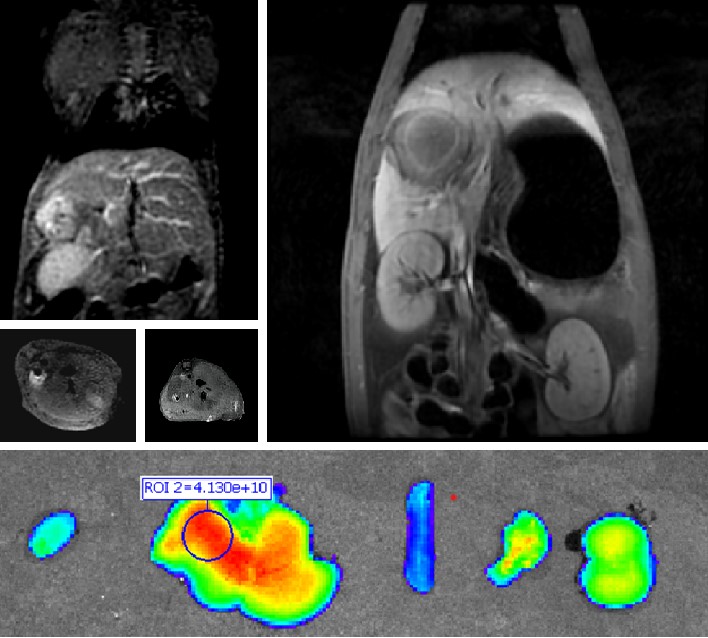

普利制药自主研发双模态造影剂PL002,首次提出通过整合磁共振技术,弥补现有荧光染料假阳性率高、透射深度有限等的短板,进而提升手术的精确性,降低手术过程中的风险,是全球首个获批临床试验的荧光/磁共振双模态造影剂,目前也已经获得美国FDA临床试验批件

640 (9).jpg